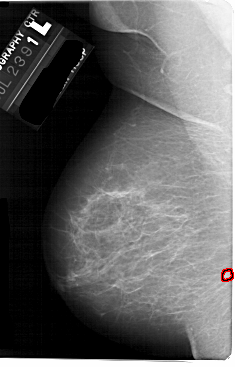

A_1738_1.LEFT_CC

LEFT_CC LINES 5491 PIXELS_PER_LINE 3481 BITS_PER_PIXEL 12 RESOLUTION 43.5 OVERLAY

FILE: A_1738_1.LEFT_CC.OVERLAY

TOTAL_ABNORMALITIES 1

ABNORMALITY 1

LESION_TYPE MASS SHAPE LOBULATED MARGINS ILL_DEFINED

ASSESSMENT 4

SUBTLETY 2

PATHOLOGY BENIGN

TOTAL_OUTLINES 1

BOUNDARY